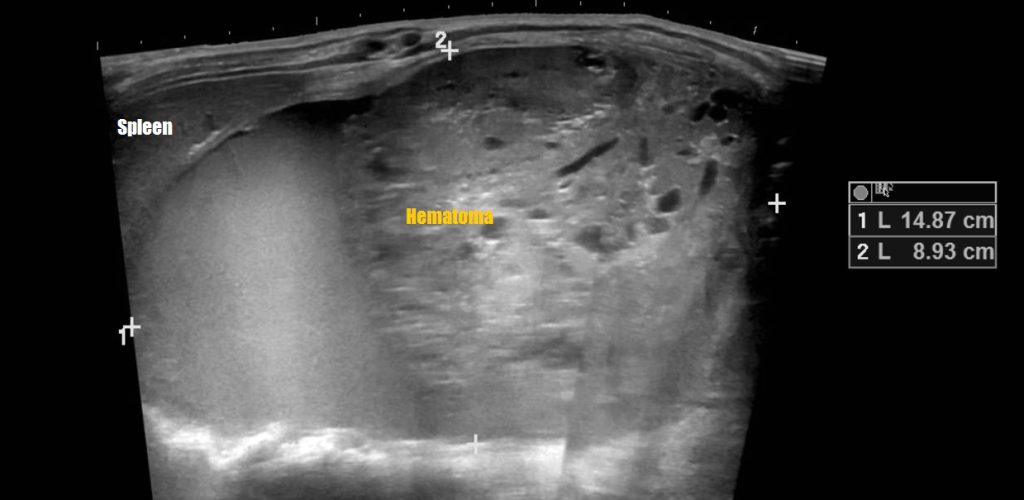

Renal Trauma

Renal trauma accounts for approximately 1-5% of all trauma admissions and as many as 10% of patients who sustain abdominal trauma. Injuries can range from contusions to life threatening injury. The types of trauma include penetrating (gsw, knife), blunt force (mva, sports injury), post procedure etc..

Patients may have abdominal/flank pain on the affected side, hematuria may also be present.